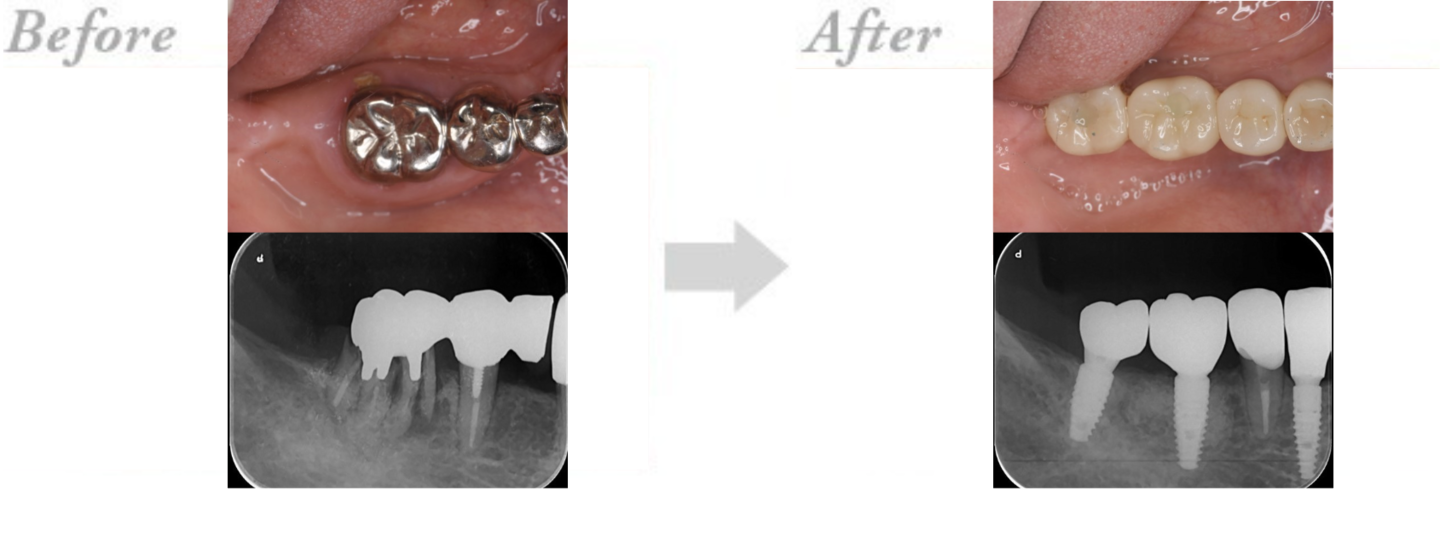

◆インプラント治療の実例 CASE1